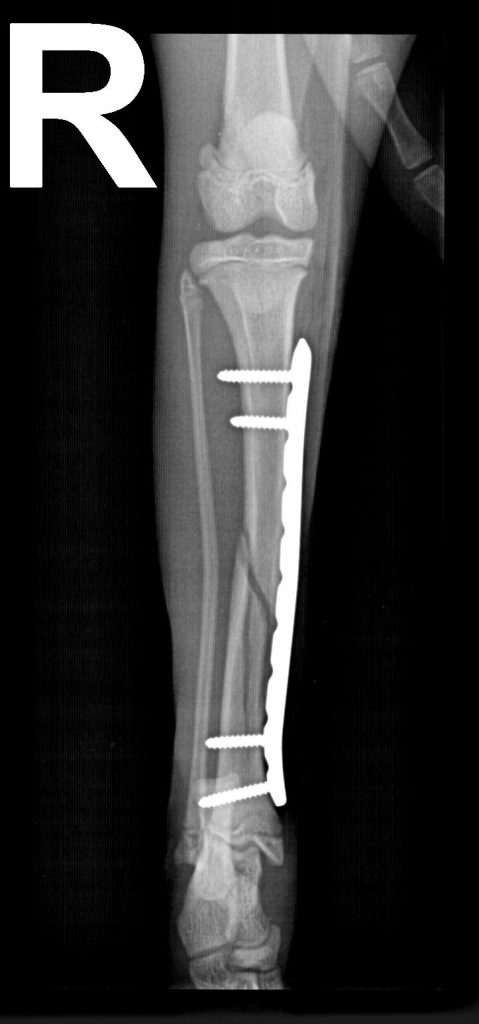

Diese OP-Technik verzichtet auf große Hautschnitte an der Bruchstelle. Statt dessen schiebt der Operateur über kleine Öffnungen eine Metallplatte unter der Muskulatur und auf der Knochenhaut über die Fraktur und verschraubt diese unter- und oberhalb der Bruchstelle. „Die Methode ist sehr weichteil- und knochenschonend, daher verringert sie das Infektionsrisiko und verursacht weniger Schmerzen“, erklärt die Ärztin.

Allerdings braucht ein Chirurg dafür viel Erfahrung und eine entsprechende technische Ausstattung. Denn um das Implantat optimal platzieren zu können, musste Dr. Layer über einen Röntgendurchleuchter den Eingriff live verfolgen. Außerdem eignet sich nicht jeder Knochen und nicht jede Fraktur für das MIPO-Verfahren. „Brüche mit Gelenkbeteiligung zum Beispiel müssen wir anders behandeln“, sagt die Ärztin.